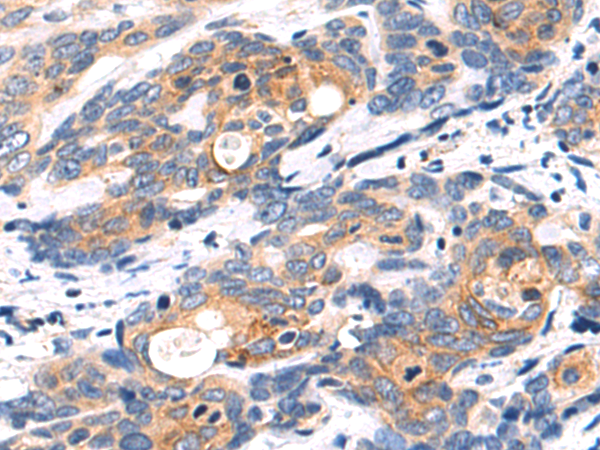

分类: 科研抗体货号: P11043别名: TBM; leB; MUC5; mucin应用: IHC反应种属: Human